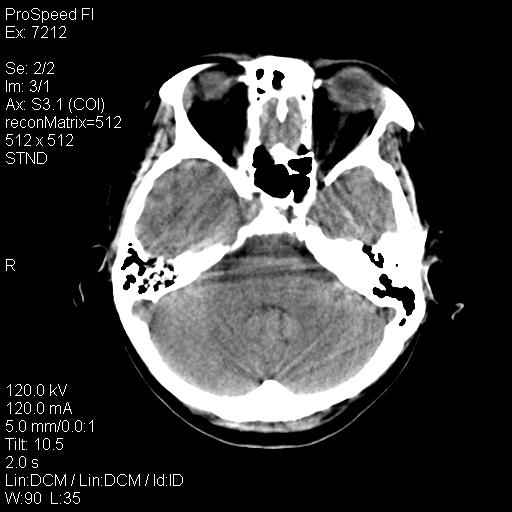

标题: CT18636:F 44Y,头痛三个月,左侧肢体麻木一周。临床诊断, [打印本页]

标题: CT18636:F 44Y,头痛三个月,左侧肢体麻木一周。临床诊断,

右额叶脑沟变浅,脑表面见新月形稍高密度影,考虑慢性硬膜下出血可能。

额顶骨多发穿凿样骨缺损区,不排除骨髓瘤等改变,进一步检查。

1)考虑左侧额颞部及右侧额部慢性硬膜下血肿(或硬膜下积液)。2)颅骨骨髓瘤不排除;建议行进一步检查。

1)右侧半卵圆中心腔隙性脑梗塞。2)考虑左侧额部慢性硬膜下血肿(或硬膜下积液)。3)颅骨骨髓瘤不排除;建议行进一步检查。